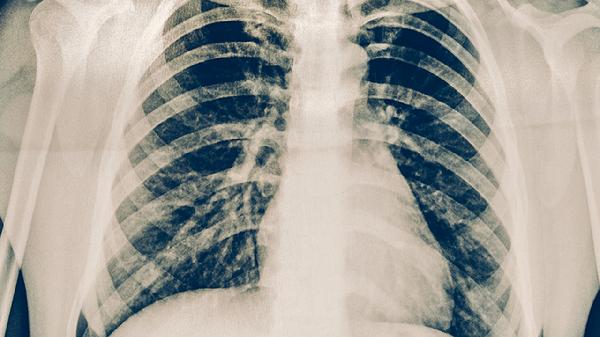

結(jié)核菌素試驗和γ-干擾素釋放試驗可用于潛伏感染篩查。胸部X線或CT能發(fā)現(xiàn)早期肺部病變。與肺結(jié)核患者有密切接觸者、免疫功能低下者應(yīng)每6-12個月進行專項檢查??人钥忍党^2周需及時就醫(yī)排除結(jié)核病。